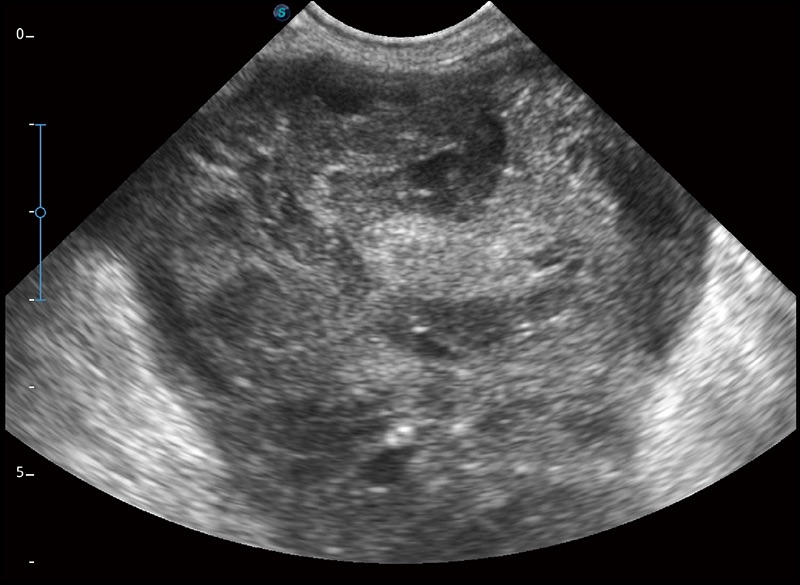

α1卓越的圖像質(zhì)量和便捷的工作流程,使每位寵物醫(yī)生都能輕松掃查。其全面的獸用應(yīng)用功能和緊湊型的結(jié)構(gòu)設(shè)計(jì),可以滿足動(dòng)物檢查的多種需要。專(zhuān)業(yè)的預(yù)設(shè)檢查模式和多領(lǐng)域測(cè)量軟件包有助于為不同類(lèi)型的動(dòng)物提供檢查, 讓寵物醫(yī)生能夠出色的完成工作。

在不犧牲時(shí)間分辨率的情況下提供出色的圖像

優(yōu)化不同角度的圖像